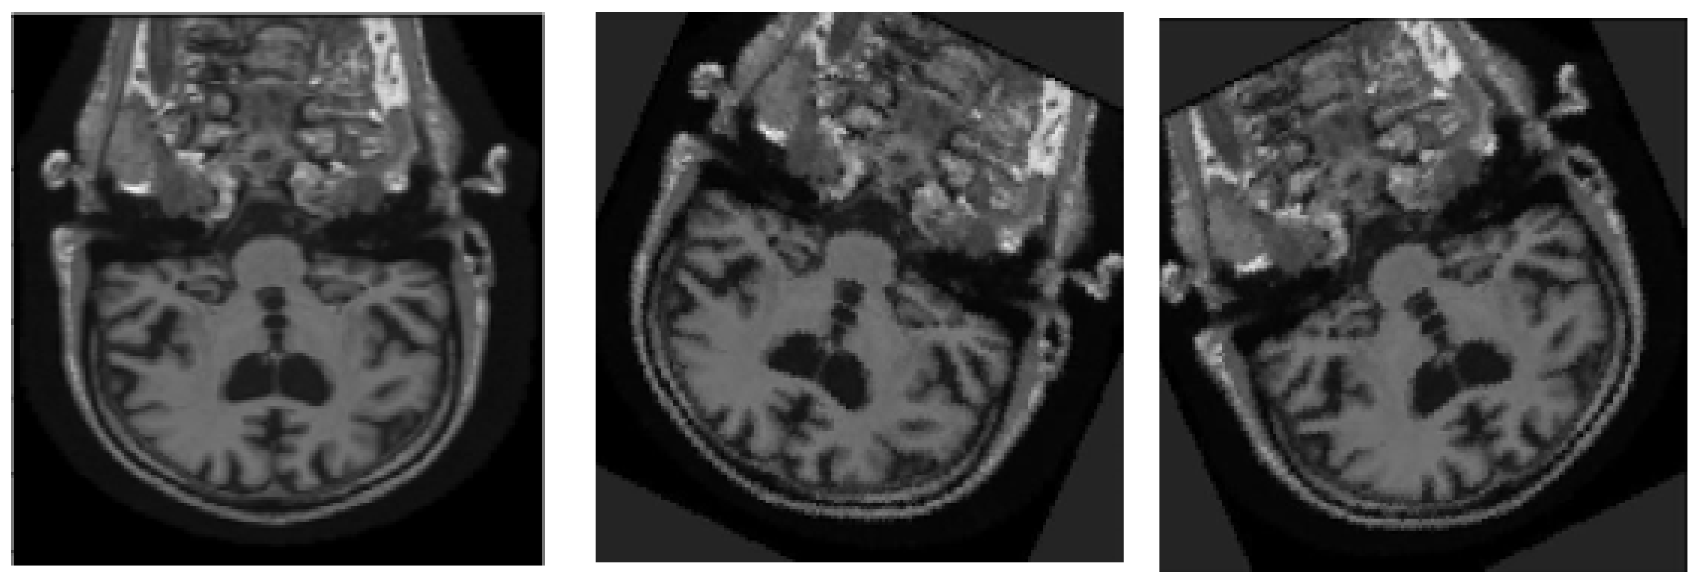

3.2. Image Fusing and Preprocessing

4.3.1. Image Fusion Performance